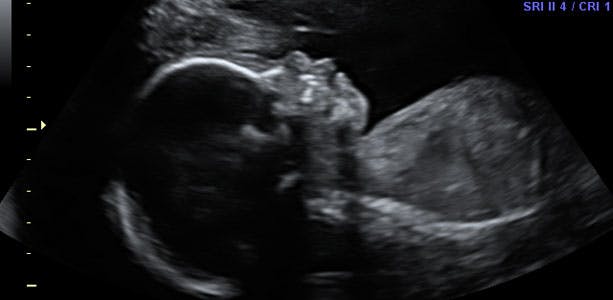

Gravid uge 23: Laver vejrtrækningsøvelser og drømmer

Selvom lungerne endnu ikke er helt færdigudviklede, laver barnet vejrtrækningsøvelser, som kan ses på ultralydsscanning. Barnet drømmer nu, og man kan se, at det har hurtige øjenbevægelser (REM). REM-søvn er den søvntilstand, hvor vi drømmer og er udtryk for høj hjerneaktivitet. I slutningen af ugen måler barnet cirka 28 centimeter og vejer omkring 650 gram. Lårbensknoglen måler cirka 3,9 cm, og hovedets diameter er cirka 5,4 centimeter.